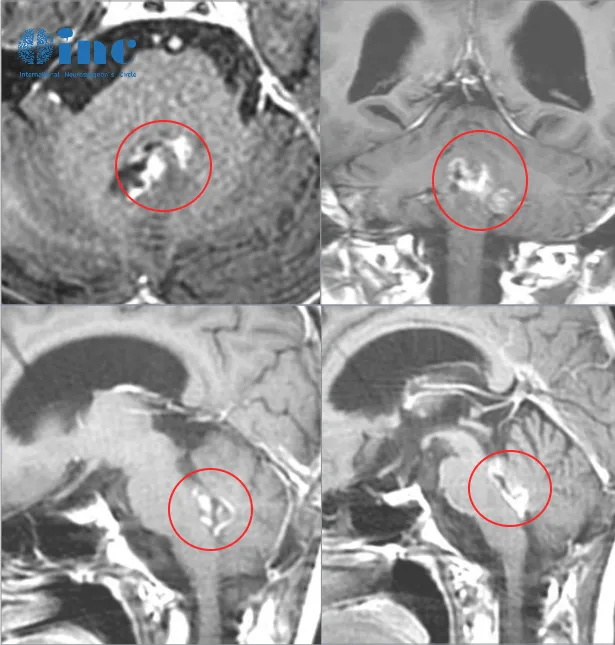

10岁男孩周周,患有四脑室肿瘤的他,一开始开颅手术后面瘫、复视、吞咽困难以及走路不稳;放疗后复查出现脑积水,行分流术;再次复查,胶质瘤复发……绝望之际找到了INC德国巴教授国内示范手术,终于获得了顺利全切、无新发手术并发症。

不明原因地头痛呕吐,当地医院检查发现颅内占位性病变,伴梗阻性脑积水。经过进一步的评估,周周被诊断为可能患有脑干及四脑室的肿瘤。

自此,开始了周周长达一年的抗击脑瘤之路。一开始在当地进行开颅手术时,“术中一过性心率下降,只能停止操作……由于在操作时肿瘤与脑于关系密切、边界不清,作为呼吸心跳中枢脑干,如果继续手术下去,很可能这个幼小的的生命就会发生呼吸心跳骤停、将带来毁灭性的结果。手术只切除了小部分肿瘤而结束。”

术后,周周的头痛和呕吐症状得到了缓解,但他却出现了面瘫、复视、吞咽困难以及走路不稳等症状,这对于年龄较小的周周来说可能是一次较大的身体和心理的考验。由于面瘫,周周脸只能一直板着,本来以为他是这么严肃,没想到他是没法笑……

术后一个月,周周接受了放射治疗,希望能够进一步控制和预防肿瘤的复发。然而,在随后的复查CT中发现他仍然有脑积水,在急诊全麻下行“右侧脑室腹腔分流术”。

后定期复查磁共振检查,近期一次检查提示小脑蚓部占位,结合病史,考虑胶质瘤复发可能伴幕上脑积水。

虽然周周的行走能力、吞咽功能较术后好转,但仍有复视和面瘫症状,完全无法微笑,做出表情。“如果一开始手术能够在更前沿的地方做就好了。”